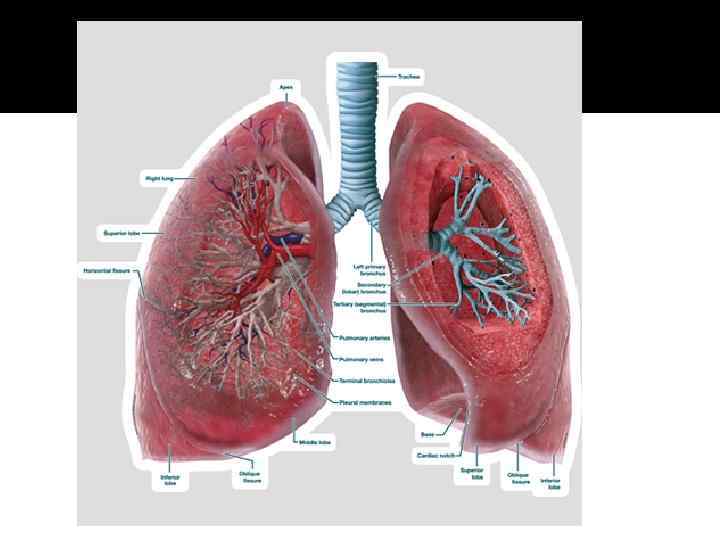

Анатомические изображения сегментов легких различных животных

Раздел: Другие животные